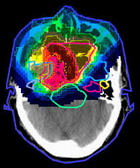

- лучевую терапию: внешнее облучение и брахитерапию;

Необходимо отметить, что медицина в Германии сейчас располагает мощнейшей диагностической базой, позволяющей выявлять те либо иные онкологические заболевания на самой начальной стадии их развития. Клиники оснащены высокоточной аппаратурой для постановки лабораторных тестов и проведения различных визуализирующих диагностических процедур: эндоскопии, рентгенодиагностики, УЗ-исследований, радиоизотопного сканирования, комбинированной томографии (PET/CT-технологии) и т.д. В стране действуют специальные профилактические скрининговые программы – Check-up, благодаря которым удается обнаружить проблему еще до возникновения клинических симптомов.